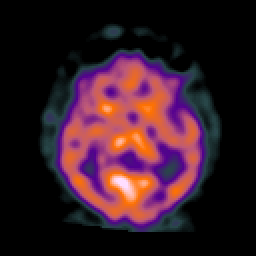

AIDS dementia: overlay -- Slice #8

[Home][Help][Clinical][Tour 1] Slice 8